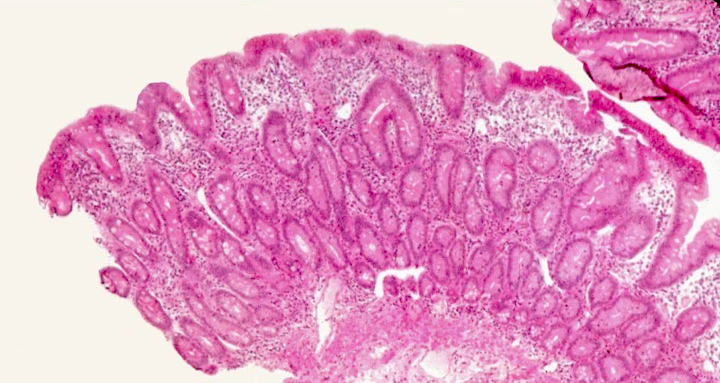

Microscopic (histologic) description

- Histological elementary lesions (Dig Liver Dis 2011;43:S385, Semin Diagn Pathol 2014;31:124):

- Villous atrophy:

- Decrease in villous height, normal villous:crypt ratio (3:1) until total disappearance of villi

- This assessment requires proper orientation of the biopsies

- Diagnostic categories are based on these elementary lesions:

- Modified Marsh-Oberhuber classification of histologic findings in celiac disease

- Different grades of duodenal mucosal lesions:

- Grade A / type 1: increased intraepithelial lymphocytes but no villous atrophy

- Grade B1 / type 2: villi still present but shortened

- Grade B2 / type 3: complete villous atrophy

Microscopic (histologic) images